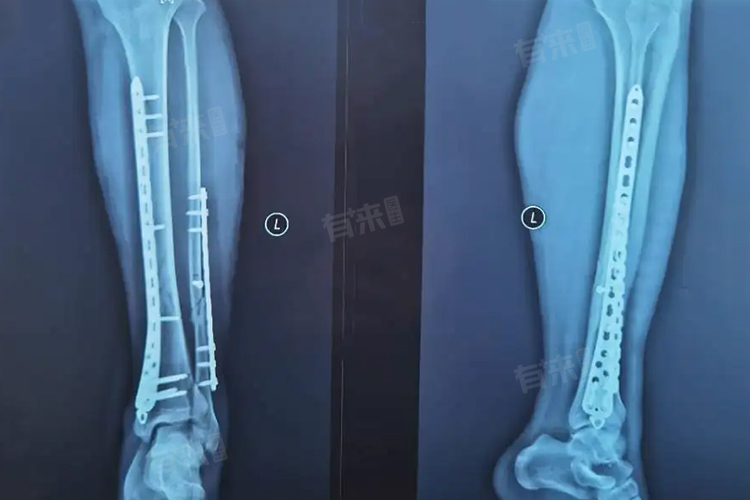

骨折打钢板后的恢复时间因多种因素有所不同,比如骨折部位与严重程度、患者年龄与身体状况等,完全恢复正常需要一定的时间和过程,可能需要3-9个月,建议患者及时就诊,尽量缩短恢复时间。

- 骨折的部位和严重程度是影响恢复时间的重要因素,如果是上肢的简单骨折,如桡骨或尺骨骨折,且骨折端对位对线良好,在钢板固定后,通常3-6个月左右可以基本恢复正常功能。